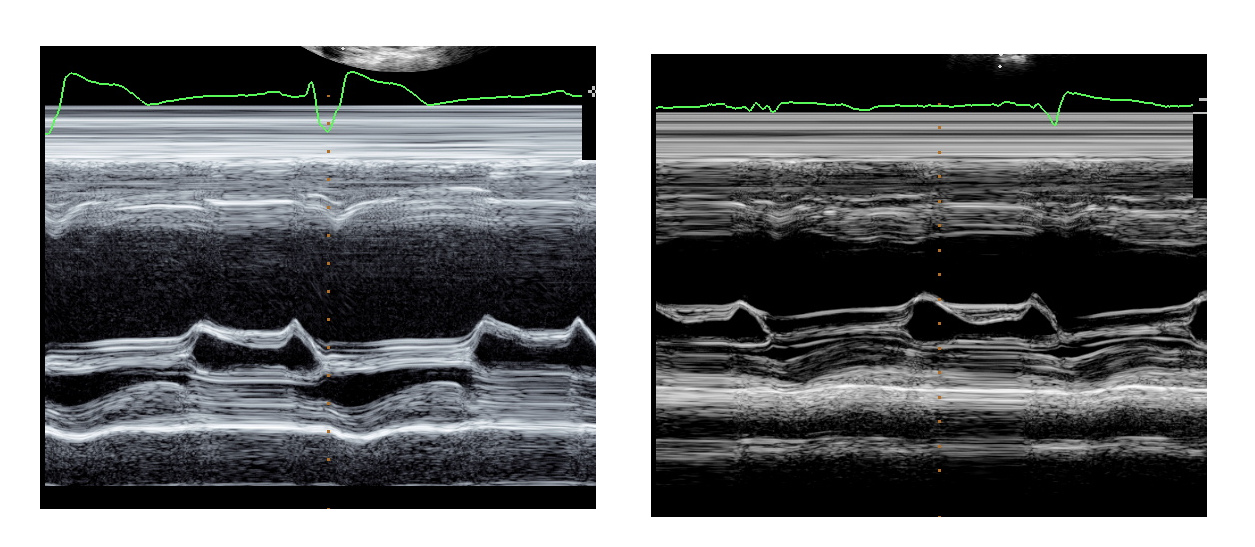

Echo - Pre and Post (3 months)

echo_pre_post.jpg

Now - 8 years later

• NYHA I

• LVEF 55%

• Beta blocker and ACEI